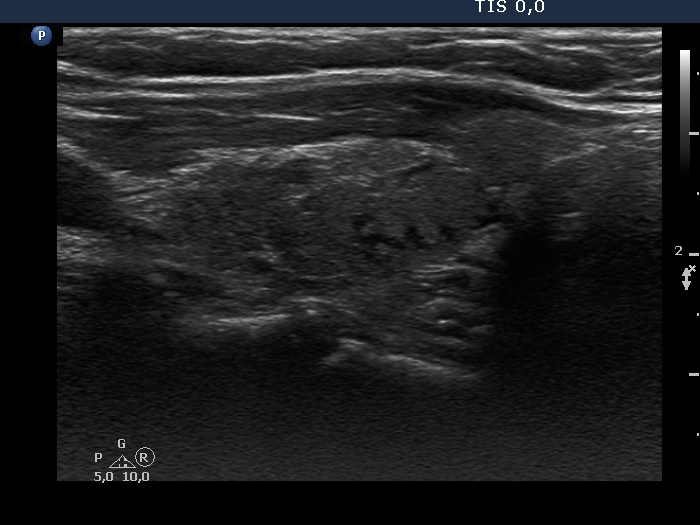

Consecutive patients with the final diagnosis of Hashimoto's thyroiditis - case 43 (1182) (ultrasonographic picture 5)

Left lobe, longitudinal view. The hypoechogenic areas correspond to more active foci of thyroiditis.